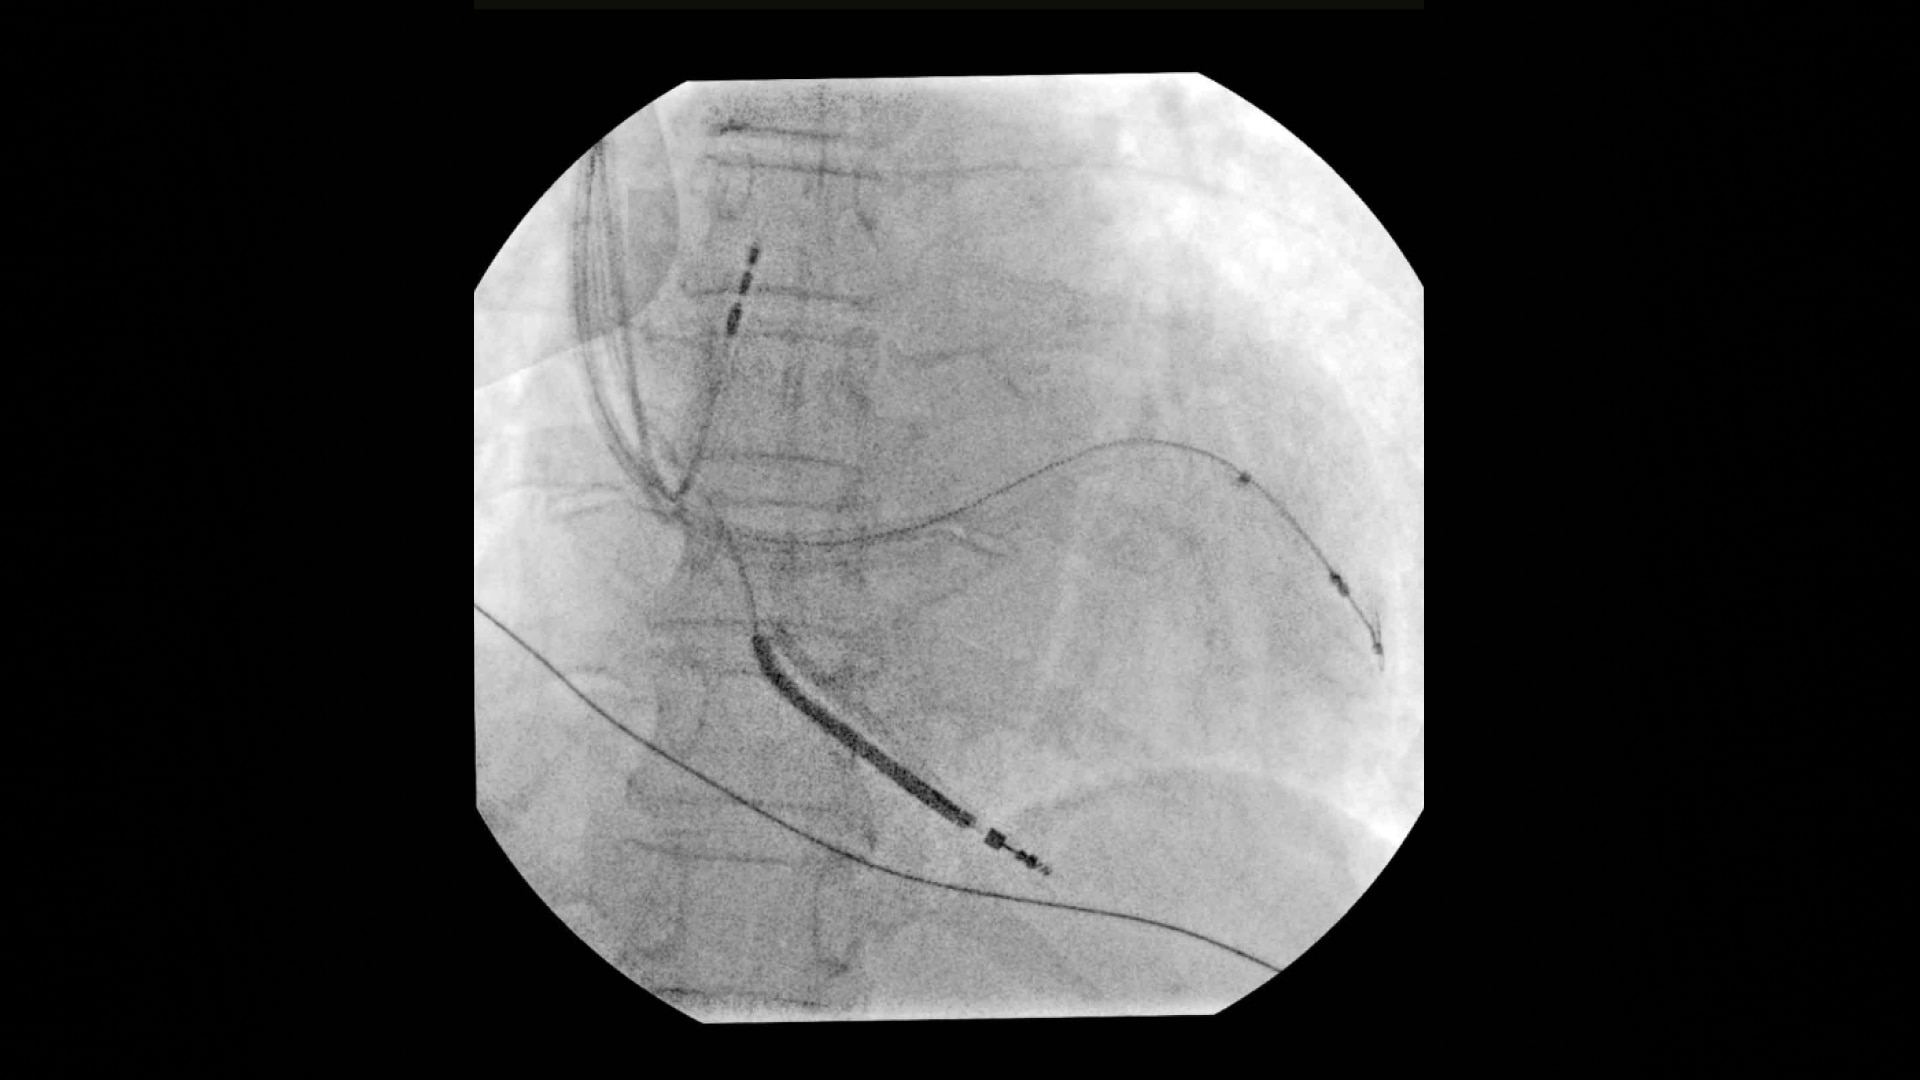

• Schrittmacherimplantationen

Die Anwender profitieren von der klaren Darstellung feinster Details – darunter Schrittmacher-Elektroden und kleinste Führungsdrähte. Dank der Dynamikbereichregelung bleibt die Bildauflösung auch bei Bewegung während des Eingriffs konstant hoch, was die klinische Sicherheit und Effizienz deutlich verbessert.